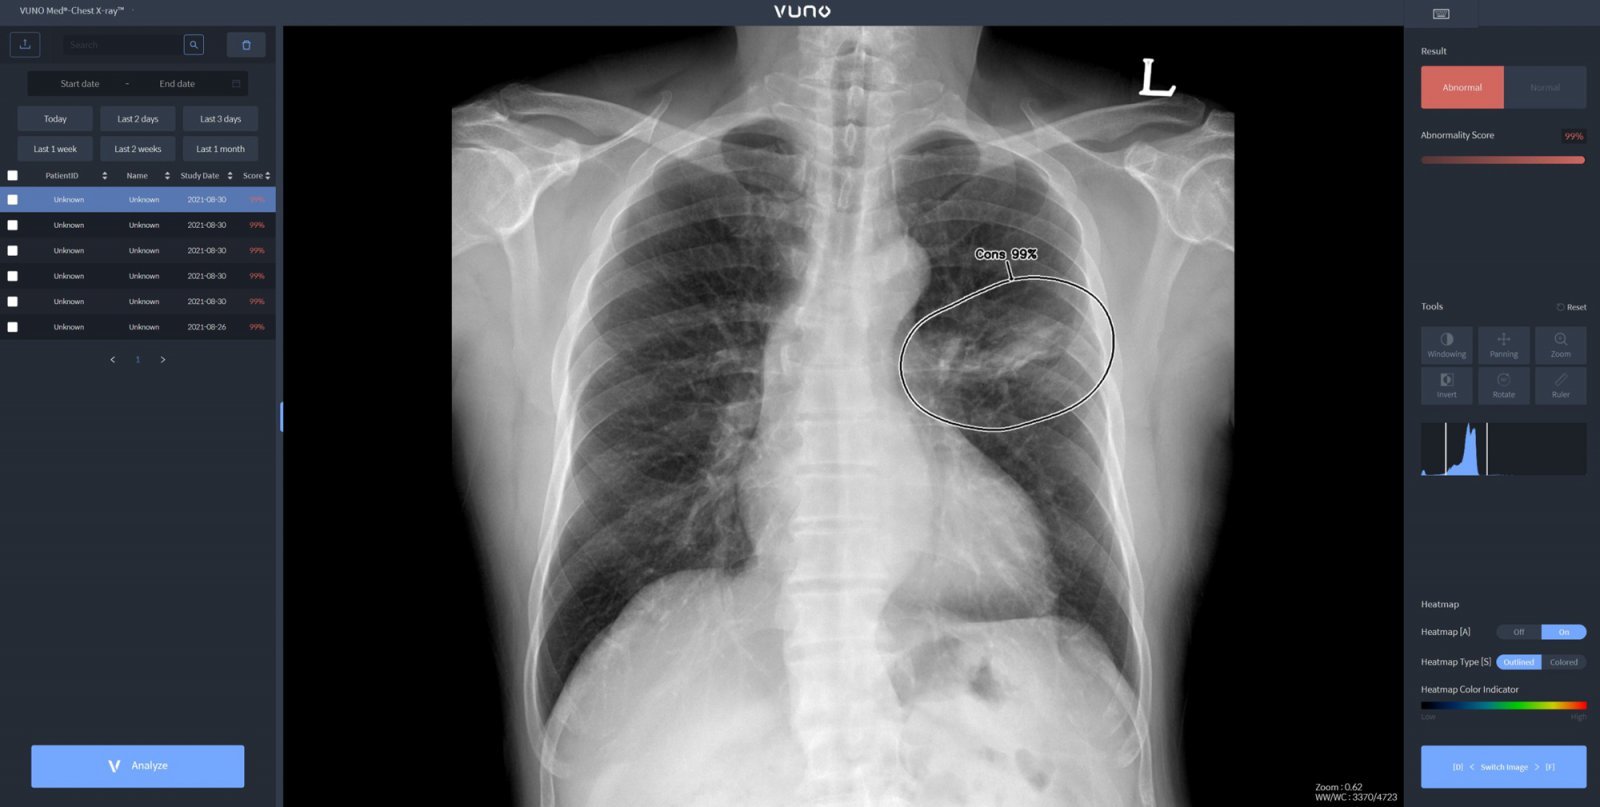

26일 의료계에 따르면 기흉은 폐에 생긴 구멍으로 공기가 새면서 폐 밖(흉막강) 안에 공기가 차는 질환이다.

기흉은 자발성 기흉과 외상성 기흉으로 구분된다. 자발성은 일차성 기흉과 이차성 기흉으로 나뉜다. 일차성 기흉은 건강한 사람에게 발생하며, 폐의 가장 윗부분 흉막에 있는 작은 공기주머니에 의해 발생한다. 일차성 기흉의 원인은 분명하지 않지만 환자의 대부분이 키가 크고 말랐거나 흡연자라는 보고도 있다. 이차성 기흉은 폐질환을 앓고 있던 사람에게 발생한다. 여기에는 결핵, 악성 종양, 폐섬유증, 만성 폐쇄성 폐질환, 폐기종 등이 있다.

기흉은 흉통(가슴통증)과 호흡곤란이 주요 증상이다. 흉통은 운동과 관계없이 발생한다. 호흡곤란은 기존에 앓고 있는 폐질환이 없다면 대부분 가벼운 정도다. 하지만 이전에 폐질환이 있었거나 기흉의 정도가 큰 경우에 심하게 나타날 수 있다.

기흉 치료는 크기가 작고 심하지 않은 경우에는 산소를 투여하면서 폐의 구멍이 저절로 아물 때 까지 기다린다. 크기가 크거나 증상이 심하다면 흉강 천자나 흉관 삽관을 하게 된다. 흉관 천자는 주삿바늘로 흉강 내 공기를 빼내어 폐를 팽창시켜 주는 방법이다. 작은 기흉이나 증상이 별로 없는 경우 사용할 수 있다. 흉관 삽관은 기흉이 발생한 흉강 내에 흉관(튜브)을 삽입하고, 반대쪽 끝부분을 물이 담긴 특수한 용기에 연결한 뒤 공기를 뽑아내어 폐를 펴주는 치료법이다.